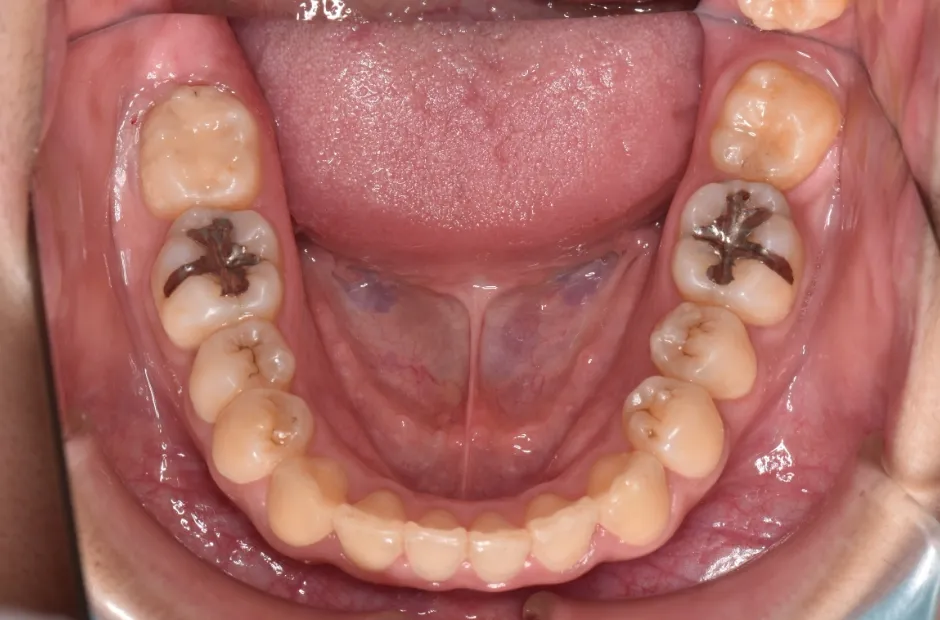

叢生

| 診断名・主訴 | 叢生 |

|---|---|

| 年齢・性別 | 43歳・女性 |

| 治療期間・回数 | 2年7か月 27回 |

| 治療に用いた主な装置 | 舌側矯正 |

| 抜歯部位 | 両顎4,4 |

| 治療費 | 100万円(税抜) |

| リスク・副作用 | 装置による違和感・疼痛・歯肉退縮・歯根吸収・虫歯のリスクなど |

治療前